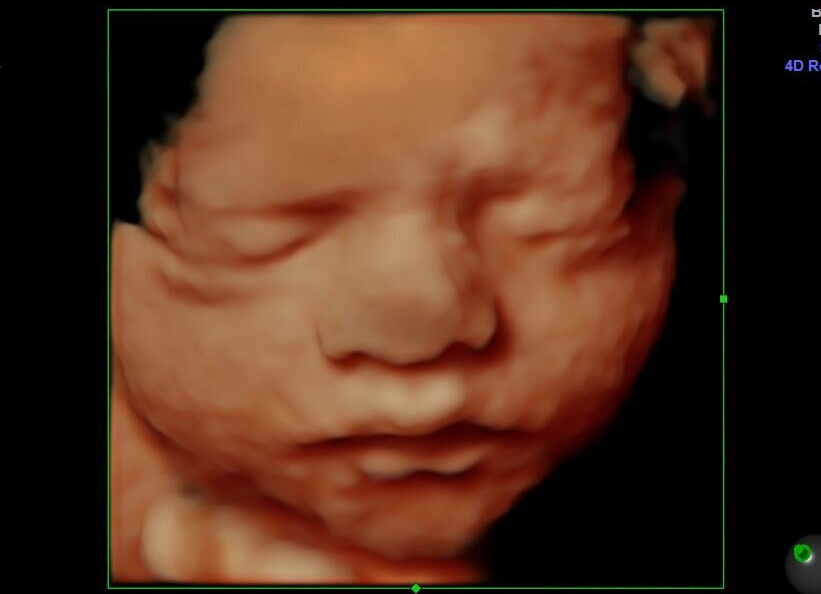

Wednesday’s lawsuit from the attorneys at Amplify Legal alleges that “Arkansas’s abortion bans are vague, confusing, and worse, extremely dangerous.” But the truth is, Arkansas’ pro-life laws are very clear — and abortion is dangerous, because it takes the life of an unborn child, and it carries serious risks and consequences for women.